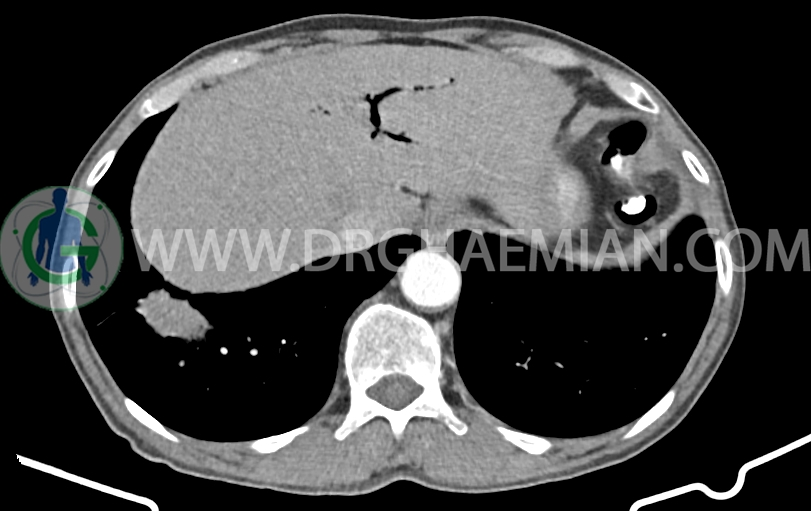

توده با حدود اسپیکوله به ابعاد mm 51x33x24 حاوی چند کانون کلسیفیه کوچک در قاعده ریه راست مجاور دیافراگم مشهود است که مطرح کننده ضایعه نئوپلازیک مثل توده اولیه و متاستاز می باشد. (نیازمند بررسی بافتی – یافته جدید نسبت به سی تی اسکن 1401/06/06 (

کانون کلسیفیه کوچک فاقد اهمیت بالینی در لوب راست کبد رویت شد

پنوموبینی در لوب چپ کبد مشهود است.